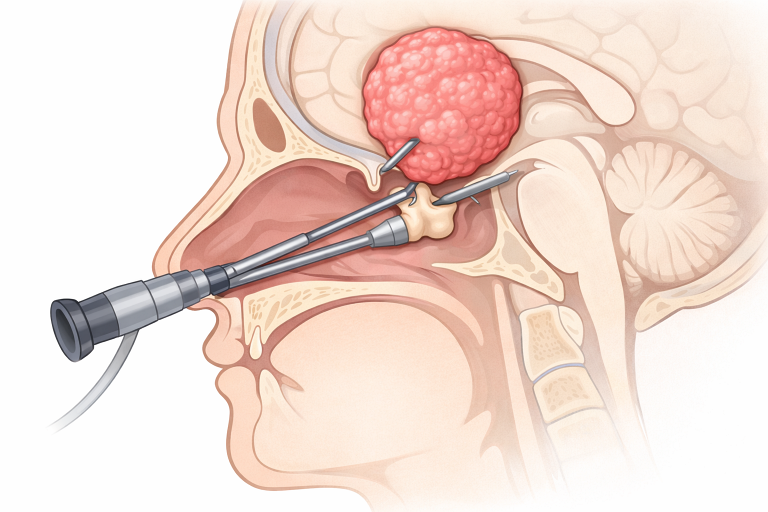

Tratamentul principal este rezecția chirurgicală, dar aceasta poate fi dificilă datorită proximității unor structuri critice (hipotalamus, chiasmă optică). Opțiunile chirurgicale includ:

Chirurgia endoscopică transsfenoidală este preferată atunci când tumora are o localizare predominant selară și supraselară inferioară.